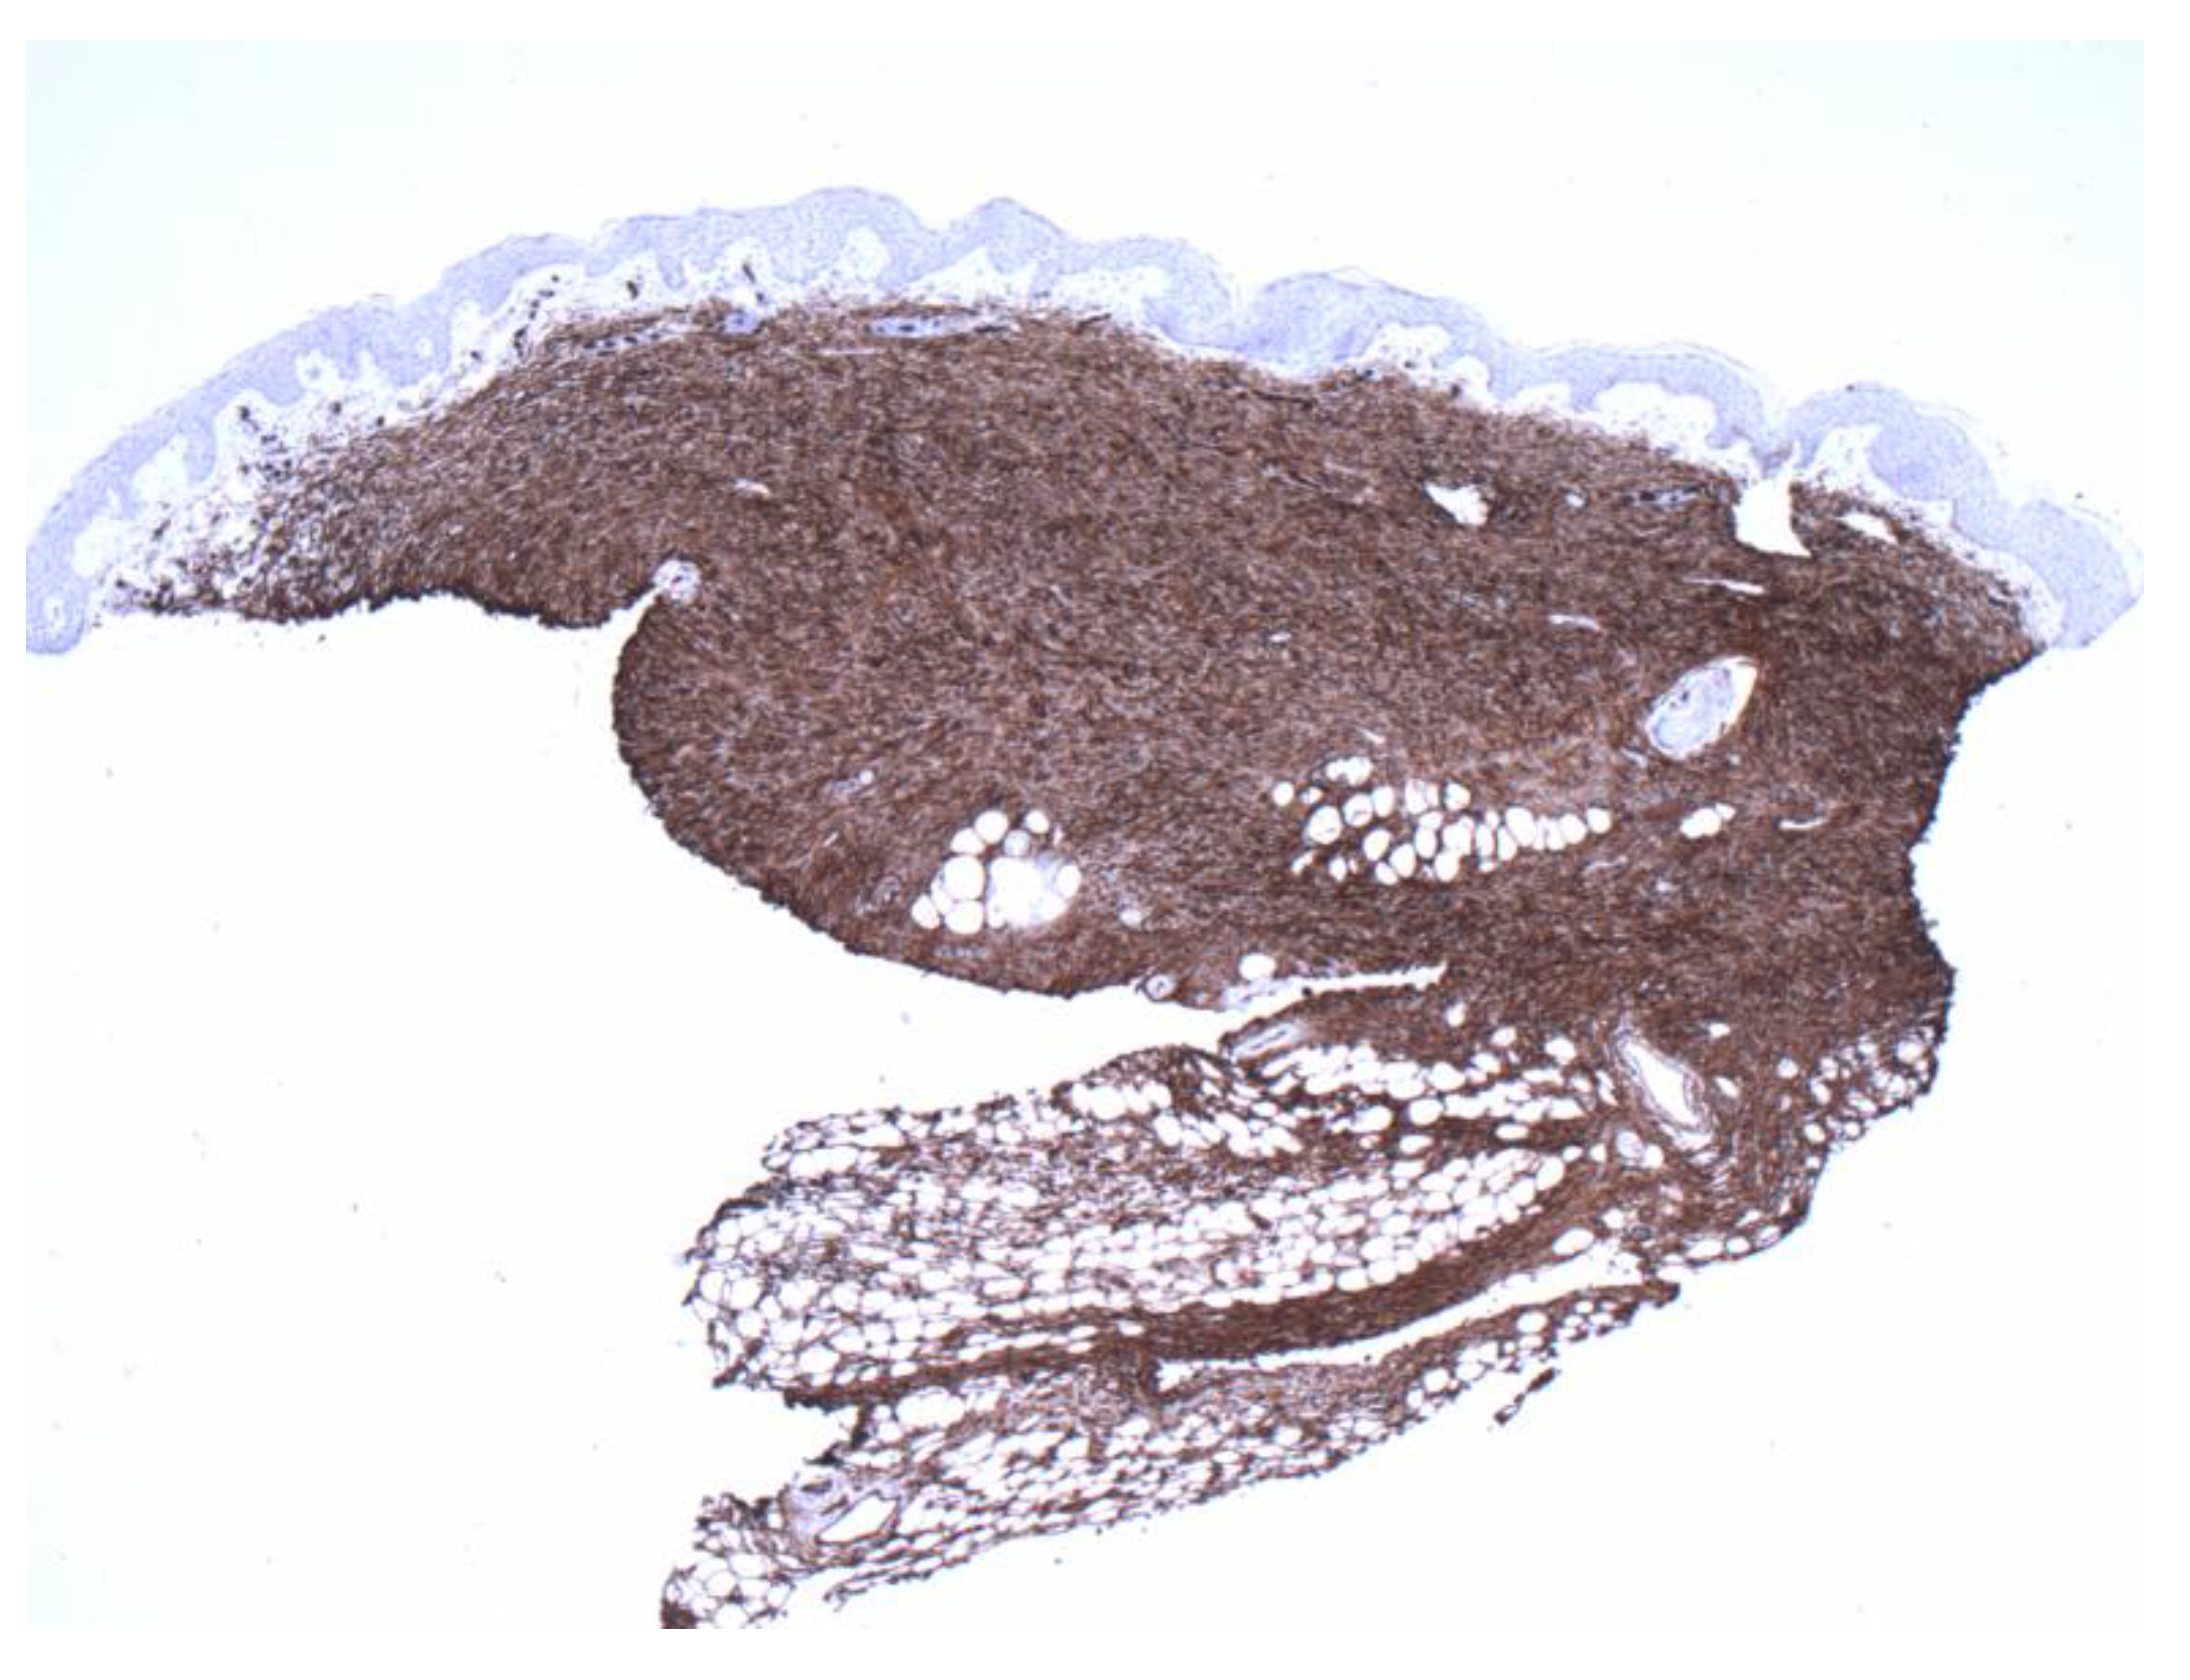

Figure 5.

The second biopsy shows diffuse and even involvement of the dermis (4×).